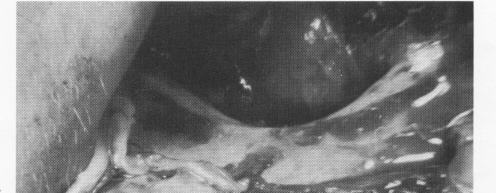

Fig. 12-14. A, The mandible has resorbed to such an ex-tent that the mental foramen is dehiscent at the residual crest. B, Resorption of this mandible left the entire mandibular canal dehiscent. The inferior alveolar nerve is seen being held with a hemostat. C, A dehiscent mandibular canal or mental foramen can be lowered and the neurovascular bundle pushed down into it, enabling a subperiosteal implant to be placed directly over the canal with no nerve impingement.

While reflecting the tissue on both buccal aspects, the operator must be exceptionally careful not to sever or injure the neurovascular bundles of nerves and blood vessels in the areas of both mental foramina. The overlying tissue should be carefully pushed downward with a blunt instrument until a semi-crescent fan-shaped area of tissue appears. This flanks the superior wall of the mental foramen. The bundle should then be more carefully separated, ex-posing more of it as well as the foramen, by pushing the fan-shaped area downward (Fig. 12-13). This should be judiciously executed prior to all impression-taking. It is necessary to exactly locate these anatomic landmarks so that every available surface of bone lying above and near them can be utilized without impinging on them. Sometimes the mandible has atrophied so much that the entire mandibular canal is dehiscent (Fig. 12-14, A and B). For such conditions, Linkow has developed a technique for lifting up the exposed mandibular nerve while lowering the floor of the mandibular canal and mental foramina at the same time with a No. 6 round bur. The nerve bundle is then gently placed back into the revised canal and pushed further into it. Since a new foramen is created, there should be no impingement from the new restoration that will be fabricated for the patient (Fig. 12-14, C) .